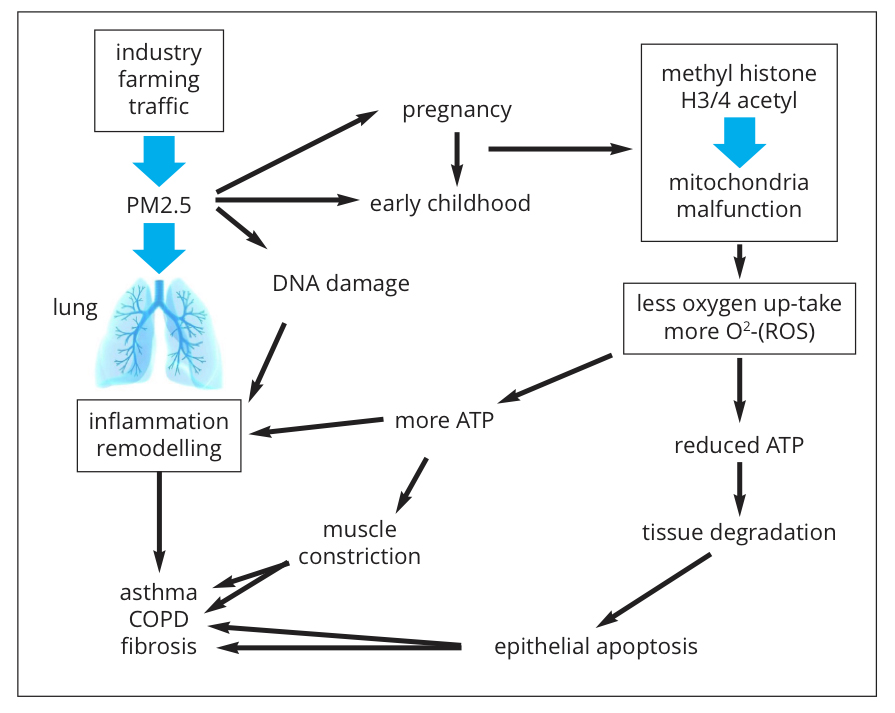

What is more worrying, are the observations that exposure to PM2.5 during embryogenesis and during early childhood (years 0-6) predisposes the lungs to develop chronic inflammatory lung diseases later in life. The molecular biological mechanism(s) by which PM2.5 leads to chronic lung inflammation remains largely unknown (Fig. 1). Toxicity due to the chemical nature of PM2.5 is one aspect of their action, but this applies mainly to soluble particles.

The size of insoluble PM2.5 compounds is the biggest concern. These small particles can be taken up not only by specialised immune defence cells, such as macrophages but also by tissue forming cells (muscle cells, connective tissue cells, etc.). Once inside a cell, the small particles activate an inflammation-like response, which aims to get rid of them, but which is most often not successful (Fig. 1).

Increasing evidence shows that PM2.5 can induce epigenetic modifications that regulate the gene activity on multiple levels, such as histone and DNA structure. Earlier, I reported that epigenetic events may underlie the “inheritable” predisposition of the lung to chronic inflammatory diseases. In this regard, mitochondria have to be considered to play a central role. The mitochondria are so-called organelles and are partly independent of the cells function and they have their own DNA and specific proteins. Mitochondria are the cell’s power stations and their function is essential for life. Modified mitochondria activity was linked to metabolic diseases, inflammation, cancer and tissue degeneration. PM2.5 can modify the function of mitochondria.

In rats, inhaled PM2.5 increased the formation of radical oxygen species (ROS) which caused the dysfunction of mitochondria. In other studies, PM2.5 reduced the oxygen consumption of mitochondrial oxygen, thereby, it decreased ATP production and caused mitochondria fragmentation. The result of this reduced energy production by mitochondria was cell death, which may be linked to the decay of the lung tissue which often occurs during the end-stage of COPD and is called emphysema. Regarding COPD, PM2.5 contained in cigarette smoke modified the methylation pattern of DNA and proteins also in non-smokers.

Concerning asthma, increased death of epithelial cells by PM2.5 exposure might explain the disrupted structure of the epithelium that lines the bronchus and is the barrier for inhaled dust, bacteria and viruses. PM2.5 caused histone hyper-methylation, thereby, modifying the accessibility of genes for transcription proteins. What is particularly worrying is the observation that such a process could happen during embryogenesis and the effects were lasting into childhood.

In animal models, exposure to PM2.5 early in life induced epigenetic predisposition to asthma-like symptoms such as, increased oxidative stress and extracellular matrix remodelling; which were handed down to the next generations. Particles that are < PM2.5, – PM0.1 –, have even been found accumulated inside mitochondria and caused severe damage to the mitochondrial DNA. Unfortunately, only a small number of studies have ever attempted to investigate this effect of small particles.